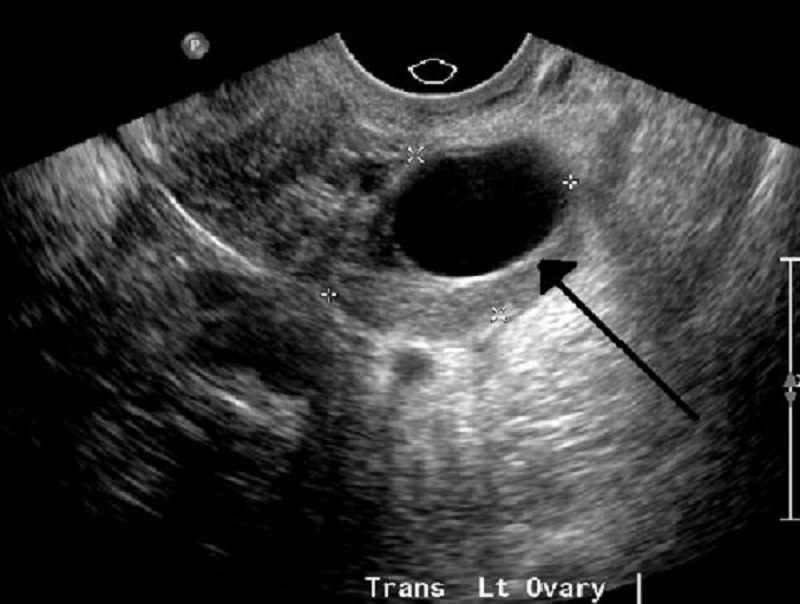

Thông qua hình ảnh siêu âm cung cấp, các bác sĩ chuyên khoa sẽ đánh giá có hay không có tình trạng u nang buồng trứng ở phụ nữ. Nếu có, những hình ảnh thu được qua sóng âm truyền về trên màn hình máy tính sẽ thể hiện chi tiết các đặc tính chính của u nang buồng trứng, như hình dạng, kích thước, vị trí và thành phần (chứa đầy chất lỏng, chất rắn hay kết hợp cả hai).

Nếu chị em bị u nang buồng trứng, phương pháp siêu âm sẽ giúp bác sĩ chẩn đoán cụ thể hơn về tình trạng này. Thông qua hình ảnh siêu âm hiển thị trên màn hình máy tính, bác sĩ sẽ xác định kích thước, mật độ, cấu trúc và hình dạng của u nang buồng trứng thời điểm hiện tại; đồng thời xác định ranh giới tiếp cận cùng ảnh hưởng của khối u đến những cơ quan xung quanh như thế nào.